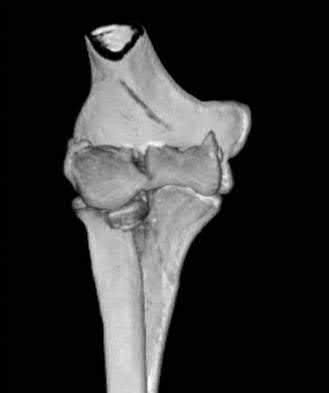

1018) A 23-year-old woman sustains the injury seen in Figures 96a and 96b. Treatment should consist of which of the following?

5. Hinged external fixation with associated ligamentous reconstruction Corrent answer: 3

This injury represents a complex partial articular fracture of the distal end of the humerus with an associated radial head fracture. Given this patient's young age, partial or complete arthroplasty is not an option. Closed reduction will lead to poor elbow function. Ligamentous repair is not indicated and external fixation will not aid in articular reduction. The patient requires open reduction and internal fixation of both components of the intra-articular injury. This is best accomplished through an extensile lateral approach or an olecranon osteotomy. Headless screws are preferred for articular reconstruction in these cases.